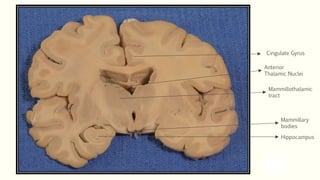

Papez Circuit

Control of emotional expression

Memory storage

Hippocampus

Mammillary

bodies

Mammillothalamic

tract

Anterior

Thalamic Nuclei

Cingulate Gyrus

Parahippocampal

gyrus